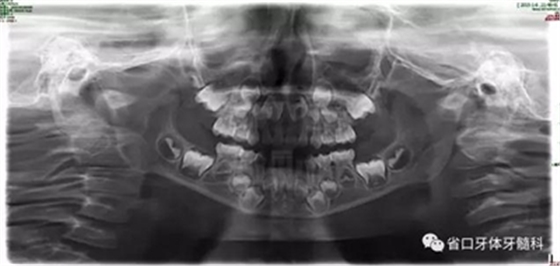

圖9 全景片

乳牙期前牙反合分為牙性、功能性和骨性

牙性前牙反合:由于乳前牙牙軸傾斜度異常導(dǎo)致;

功能性前牙反合:由于乳前牙咬合干擾,誘導(dǎo)下頜向前。

骨性前牙反合:由于上頜骨發(fā)育不足或者下頜發(fā)育過度導(dǎo)致前牙反合。

乳牙期前牙反合治療前先鑒別反合屬于牙性還是骨性反合,